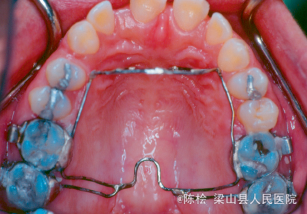

诊断:开合 治疗:双侧第一第二磨牙带环上制作TPA,同时弓丝伸至前牙段弯成腭刺,腭刺破除伸舌吞咽的不良习惯,TPA压低双侧后牙,降低后牙槽高度,改善开合.

对于开合病人,光是压低后牙可能效果不是很好,应把改不良习惯的装置一同考虑进去才能达到事半功倍的效果。该装置既包含腭刺又焊有TPA,一举两得,值得推广。